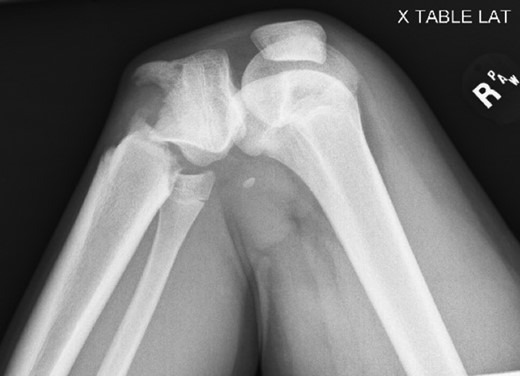

Patient is a 14-year-old male who slipped and fell while jumping off of a diving board and landed onto a flexed right knee. The patient was stable on presentation and neurovascularly intact with the knee locked in flexion. Skin was tenting anteriorly over the tibial tubercle and his compartments were swollen but compressible. A single plain film view (Fig. 1) was obtained prior to orthopaedic consultation. Closed reduction under sedation and splitting was attempted in the ED with partial but unsatisfactory improvement. Post-reduction radiographs (Fig. 2) demonstrated a tibial tubercle fracture with extension through the entire proximal tibial physis with metaphyseal involvement posteromedially. We classified this as a type IV tibial tubercle fracture, Salter–Harris II variant. In conjunction with patient and family we planned for urgent closed versus open reduction and application of knee-spanning external fixator. Immediately prior to surgery in the pre-operative holding area, the patient noted increasing right leg pain. In the operating room (OR), a marked increase in swelling with tense skin was observed. Due to rapidly progressive swelling and nature of the fracture, the decision was made to proceed with a 4-compartment fasciotomy of the right leg. The medial-sided fasciotomy (Fig. 3) revealed significant bulging of the superficial and deep compartments; however, the anterior and lateral compartments were less swollen. The fracture was unable to be closed reduced intraoperatively, therefore proximal extension of the medial fasciotomy wound was performed to open and reduce the fracture under direct visualization. Anatomic reduction was achieved and a knee-spanning external fixator was applied (Fig. 4). Approximately 72 hours later the patient was brought back to the OR for irrigation and debridement, lateral wound closure, and medial wound vacuum placement. Another 72 hours later, he returned to the OR for removal of the external fixator, ORIF, and split-thickness skin grafting of the medial fasciotomy site. An anterolateral approach was used with a 3.5 mm proximal tibial locking plate (Fig. 5). At most recent follow-up (Fig. 6), six months post-op, the patient is pain free, ambulating without assistive device, and has returned to all desired activities.

AP and lateral radiographs after attempted closed reduction which reveal type IV tibial tubercle fracture with posteromedial metaphyseal extension (Salter–Harris II variant).